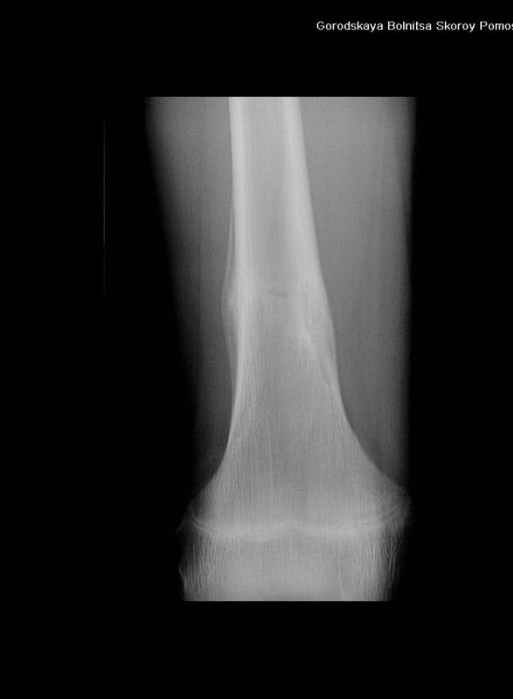

Анамнез практически никакой: в следствие травмы (растяжение связок коленного сустава) от 07.11.2004 выполнены Rg-граммы в травмпункте и обнаружено опухолевидное образование. Первичные Rg-граммы я не публикую, так как они заметно худшего качества, да и динамики за прошедшие три недели не отражают. Болевой синдром купирован в течение трёх дней. В настоящий момент мальчика ничего не беспокоит. Ходьба не нарушена, опухоль пальпируется с трудом по задней поверхности в н\3 правого бедра, пальпация безболезненна, объем движений в суставах правой нижней конечности полный и симметричный. Кожа над опухолью не изменена.В нашей клинике проведено дополнительное обследование: общие анализы крови и мочи, биохимия крови без особенностей. Выполнены Rg-граммы на цифровом Siemens обычные и продольные томограммы срезами 3-5 мм, а также компьютерная томография поперечными срезами по 5 мм. Прошу обратить внимание, что на приведённых томограммах видны две полости 10х15 мм и 15х60 мм. Также имеются два опухолевидных образований наслаивающихся друг на друга: уплощённое и вытянутое 10х100 мм и элипсовидной формы 15х30 мм. Это хорошо заметно на фото a_1.jpg c_1.jpg и d_1.jpg. Плотность внутри полостей 125% от плотности костномозгового канала, плотность наружного опухолевидного образования 55% от плотности кортикального слоя. Также отмечается линия перелома по центру наружного опухолевидного образования.Исходя из полученных данных мнения в плане диагноза несколько разделились от 1)сочетания кортикальной фиброзной дисплазии и латентно протекавшего маршевого перелома н\3 правого бедра до 2)остеосаркомы. В отношении первого варианта не сходится отсутствие клиники при переломе такой крупной кости как бедро, второй вариант вообще оставлю без комментария, ибо некомпетентен. Хотелось бы услышать мнения коллег, с удовольствием ознакомлюсь с любыми предположениями и замечаниями.С уважением, Александр Е. КлоковОтделение детской ортопедии и травматологииБСМП г. Мурманска.